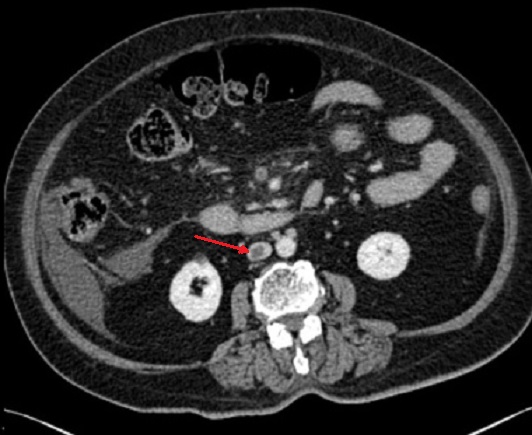

Image d'une thrombus de la

veine cave inferieure ( fleche rouge ) et image de

epaissisement a defaut de rehaussement de la paroi

de l'intestin . Ischemie mesenterique veineux de

l'intestin . Image radiologique TDM en coupe axiale

phase veineuse . |